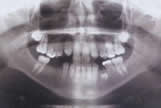

Diş röntgeni dişlerin, kemik ve dişetlerinin klinikte muayene ile görünmeyen kısımlarını göstermeye yarayan bir resimdir.

Diş röntgeni dişhekiminin dişler ya da çenelerle ilgili problemleri teşhis etmesine yardımcı bir yöntemdir. Örneğin ağız içi muayene ile sadece büyük çürükler teşhis edilebilirken, röntgenle başlangıç çürükleri tespit edilebilir. Ya da ağızdaki absenin hangi dişten kaynaklandığı, dişlerdeki yapı bozuklukları, kök kırıkları, kist ya da tümörler röntgenle tespit edilebilir.